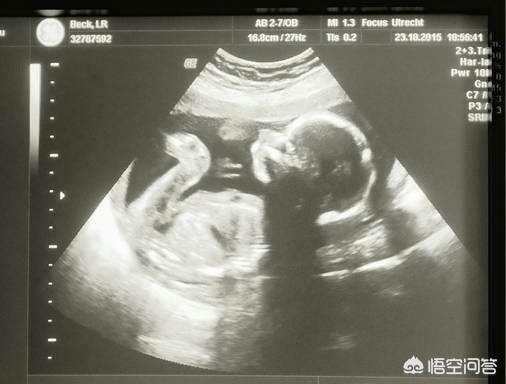

Cependant, en réalité, l'échographie 4D n'améliore pas l'efficacité du diagnostic par rapport à l'échographie ordinaire, et les hôpitaux publics ne mettent pas en œuvre de programmes d'échographie 4D.

La 3D ou la 4D n'est pas un facteur qui affecte les résultats de l'échographie, l'expérience de l'échographiste est le facteur le plus important.

Il est donc important de se rendre dans un établissement médical de soins de maternité et de subir un test de maternité conformément aux exigences, afin de prévenir autant que possible les malformations congénitales.